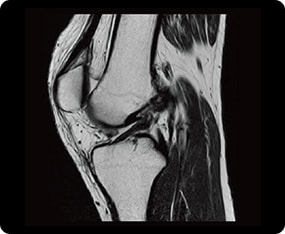

その他MRI検査の症例画像

膝関節